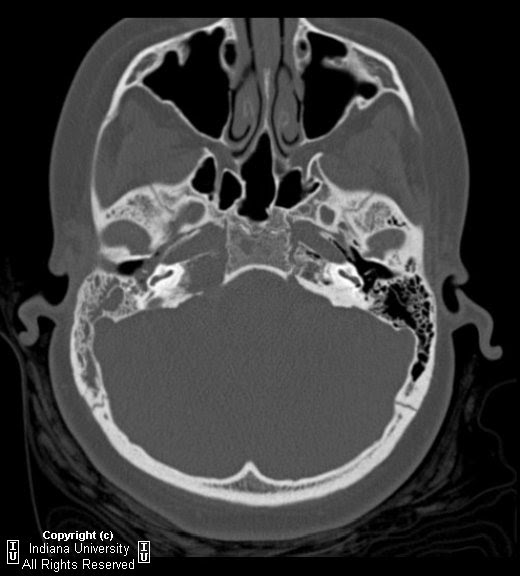

Neuroradiology On The Net: Right Petrous Apicitis (Gradenigo's Syndrome

petrous right gradenigo syndrome clinically neuroradiology